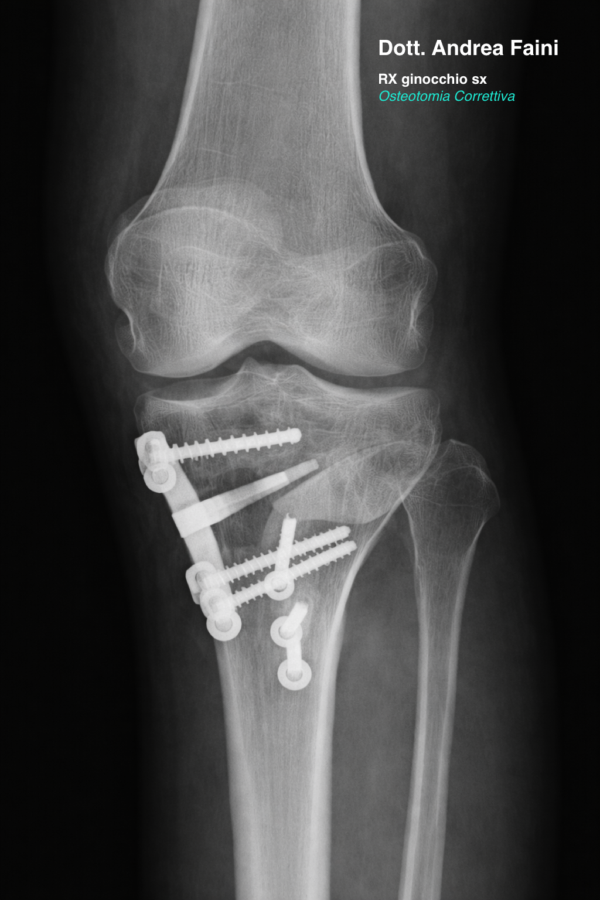

In un’osteotomia di ginocchio, la tibia e/o il femore, vengono tagliati e riallineati per redistribuire correttamente la forze all’interno del ginocchio. Al termine, i segmenti tagliati vengono ricongiunti usando dei mezzi di sintesi (placca e viti in titanio).

Utilizzata principalmente per correggere il ginocchio varo, prevede una incisione sulla faccia mediale della tibia prossimale, il taglio e il rimodellamento dell’osso, seguito da correzione dell’asse e fissazione con placca dedicata.

Osteotomia femorale

L’obiettivo in entrambi i casi è ottenere un asse neutro o leggermente ipermobile, in modo da distribuire in maniera più equilibrata il peso corporeo sull’articolazione del ginocchio.

Il percorso inizia con una valutazione specialistica ortopedica e l’esecuzione di radiografie sotto carico e, se necessario, una risonanza magnetica. Questo permette di misurare la deviazione dell’asse e pianificare con precisione la correzione.

Il chirurgo esegue un taglio controllato dell’osso tibiale o femorale, effettua la correzione dell’asse e stabilizza il segmento osseo con placche e viti. L’intervento dura in genere 1-2 ore.